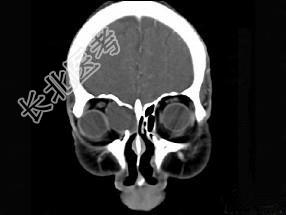

- 多项选择题女性38岁,右侧眼球运动障碍伴眼球突出4个多月, CT扫描如图,请选择正确的描述和答案 ( )

A、右侧筛窦内可见囊性肿块影,边缘光整

B、囊性肿块向右侧眼眶内突入,压迫内直肌

C、右侧眶内壁呈受压变薄、断裂

D、考虑为右侧筛窦黏液囊肿

E、考虑为筛窦癌